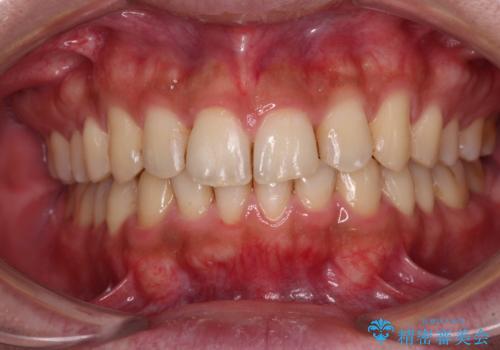

上顎骨拡大を併用したインビザライン矯正

- 上下のデコボコと奥歯の咬みにくさを気にして来院された患者様です。

上顎骨の幅が下顎骨よりも小さいので、拡大装置により骨幅を広げて上下関係を改善し、その後インビザラインにて歯並びを整えることとしました。

上下の骨幅を改善したことで、スムーズに歯列矯正を行うことができました。

矯正治療中に近医で銀歯を外す治療を開始したため、治療後に奥歯の咬み合わせが不十分ですが(こちらは近医での治療により改善するとのこと)、歯列と咬み合わせが改善され、患者様には大変満足していただきました。